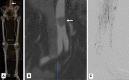

Figures